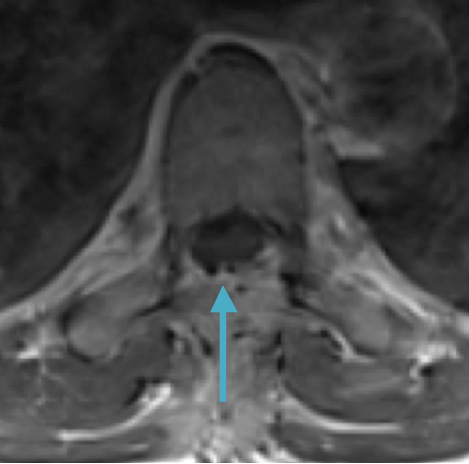

Postoperative MRI T1w demonstrating interval resection with cord re-expansion (blue arrow)

Postoperative MRI T1w demonstrating a gross total resection